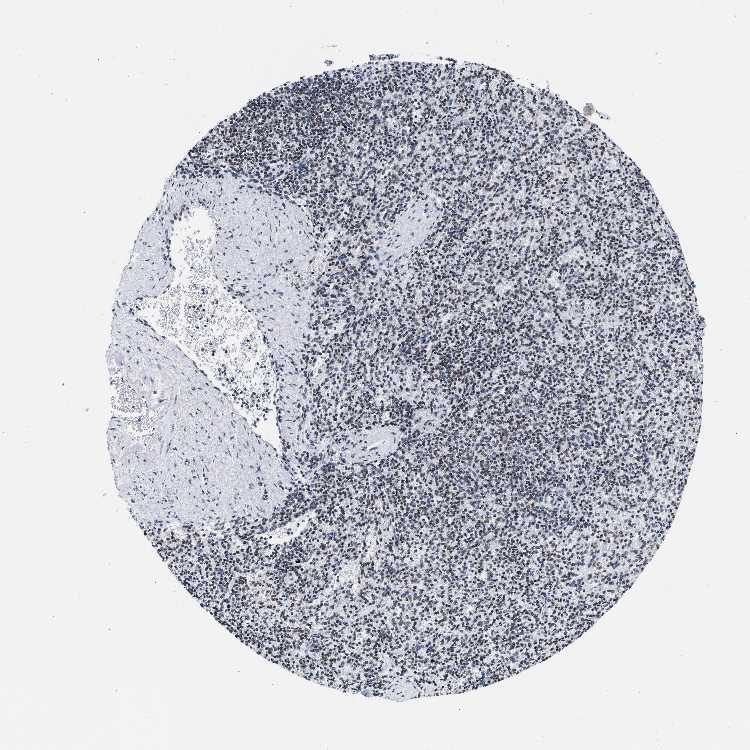

SPLEEN - Antibody stainingi

Antibody staining in the annotated cell types in the current human tissue is reported as not detected, low, medium, or high, based on conventional immunohistochemistry profiling in selected tissues. This score is based on the combination of the staining intensity and fraction of stained cells.

Each image is clickable and will lead to virtual microscopy that enables deeper exploration of all samples and also displays staining intensity scores, fraction scores and subcellular localization as well as patient and tissue information for each sample.

Antibody HPA018403

Cells in red pulp Medium

Cells in white pulp Medium